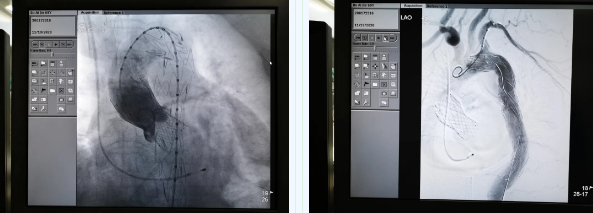

張金洲副院長關注著手術的每一個細節,從建立軌道、跨瓣、釋放瓣膜、支架定位、造影和食道超聲確認,每一步都緊張而有序地進行著。為了最大程度保障病人安全,心臟外科程亮副主任也帶隊建立動靜脈入路,以備緊急體外循環。經過團隊每一位成員的密切配合,在近四小時的緊張奮戰之后,“TAVR TEVAR”復合手術順利完成;經過造影和食道超聲證實:人工主動脈瓣無返流無瓣周漏、冠脈顯影良好,主動脈覆膜支架無內漏無移位。